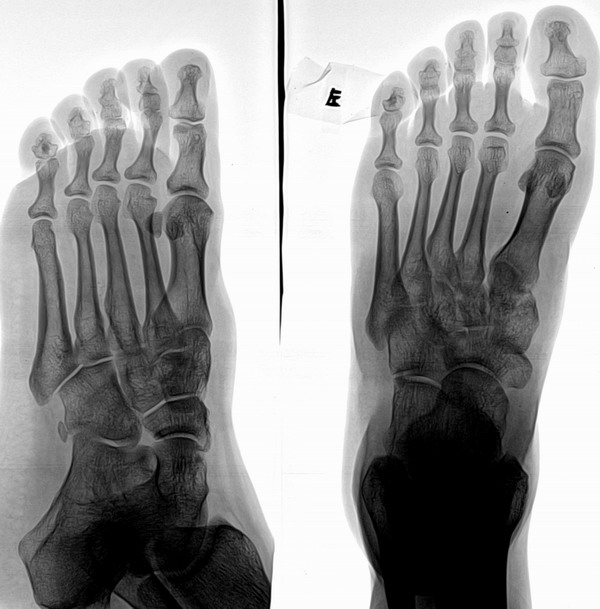

大家看看是正常还是异常?

病人的受伤部位不在这里,只是想让大家看看!

以下是引用浮华在2007-5-22 18:39:00的发言:[br]小趾中节趾骨高密度影,边界清,无明显骨质破坏--骨岛?

小趾中节趾骨高密度影,边界清,无明显骨质破坏--骨岛?